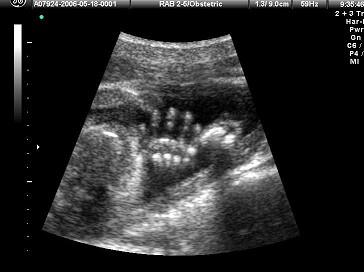

如图,超声显示的是胎儿的哪一部位?(?)A.手B.脚C.腿D.腹部E.颈部

问题 如图,超声显示的是胎儿的哪一部位?(?)

选项 A.手 B.脚 C.腿 D.腹部 E.颈部

答案 A